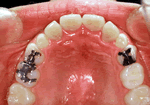

・機能的矯正装置について

当院では咬合誘導を基本方針としています。

永久歯が生えるまでの歯並びだけではなく、お口の中の環境を改善し、顔面の成長を促進させる為に機能的矯正装置をおもに使用いたします。

特に受け口や出っ歯の目立つお子様に有効です。

この装置はお子様の顔の筋肉の力によって歯及び顎の移動を行うものです。

主に5歳から10歳くらいに用いられます。血縁者に顔が似ている歯並びの場合も使えます。